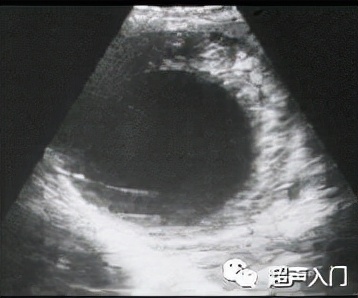

1、单囊型

表现为肝内出现单个圆形或类圆形无回声区,囊壁增厚完整,为中高回声,可呈双层,同时可出现细小的点状反射堆集于囊底,随体位改变而漂浮,形成“飘雪”征。

单囊型(CE1)

图源:人卫出版社教材及课件